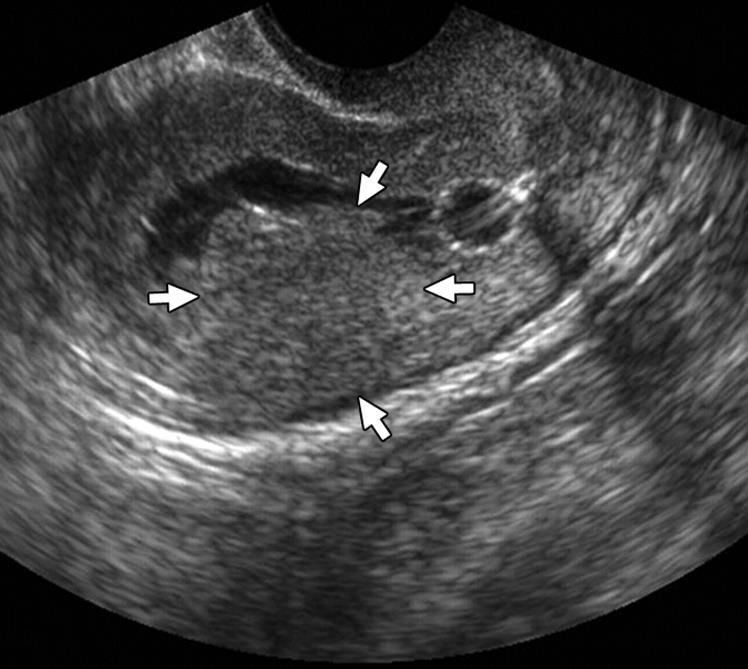

Isthmocele